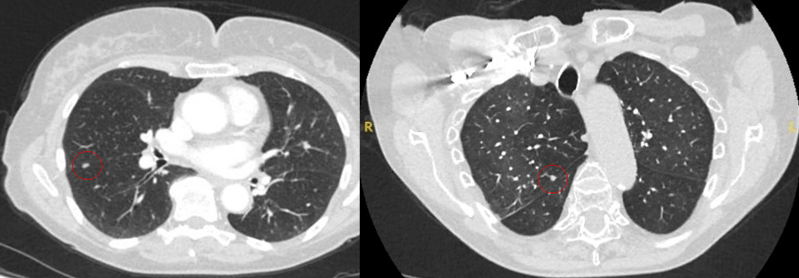

O aparecimento da fissura adjacente, bem como quaisquer "marcas" pleurais visíveis, são sinais que devem ser considerados na avaliação de nódulos pulmonares solitários perifissurais ou periféricos. Uma fissura retraída associada a um nódulo não liso aumenta a possibilidade de neoplasia maligna.[33][34][Figure caption and citation for the preceding image starts]: Cortes de tomografia computadorizada (TC) de dois casos com nódulos perifissurais benignos. Observe as margens lisas e a fissura adjacente normal e intactaDo acervo de Dr. George Tsaknis, MD, PhD, FRCP (Londres), MRQA, MAcadMEd, PGCert; usado com permissão [Citation ends].

[Figure caption and citation for the preceding image starts]: Tomografia computadorizada (TC) mostrando exemplos de nódulos perifissurais malignos. Observe a borda espiculada dos nódulos e a evidente retração da fissura adjacente. Ambas as análises de tecido de ressecção confirmaram adenocarcinoma de pulmãoDo acervo de Dr. George Tsaknis, MD, PhD, FRCP (Londres), MRQA, MAcadMEd, PGCert; usado com permissão [Citation ends].